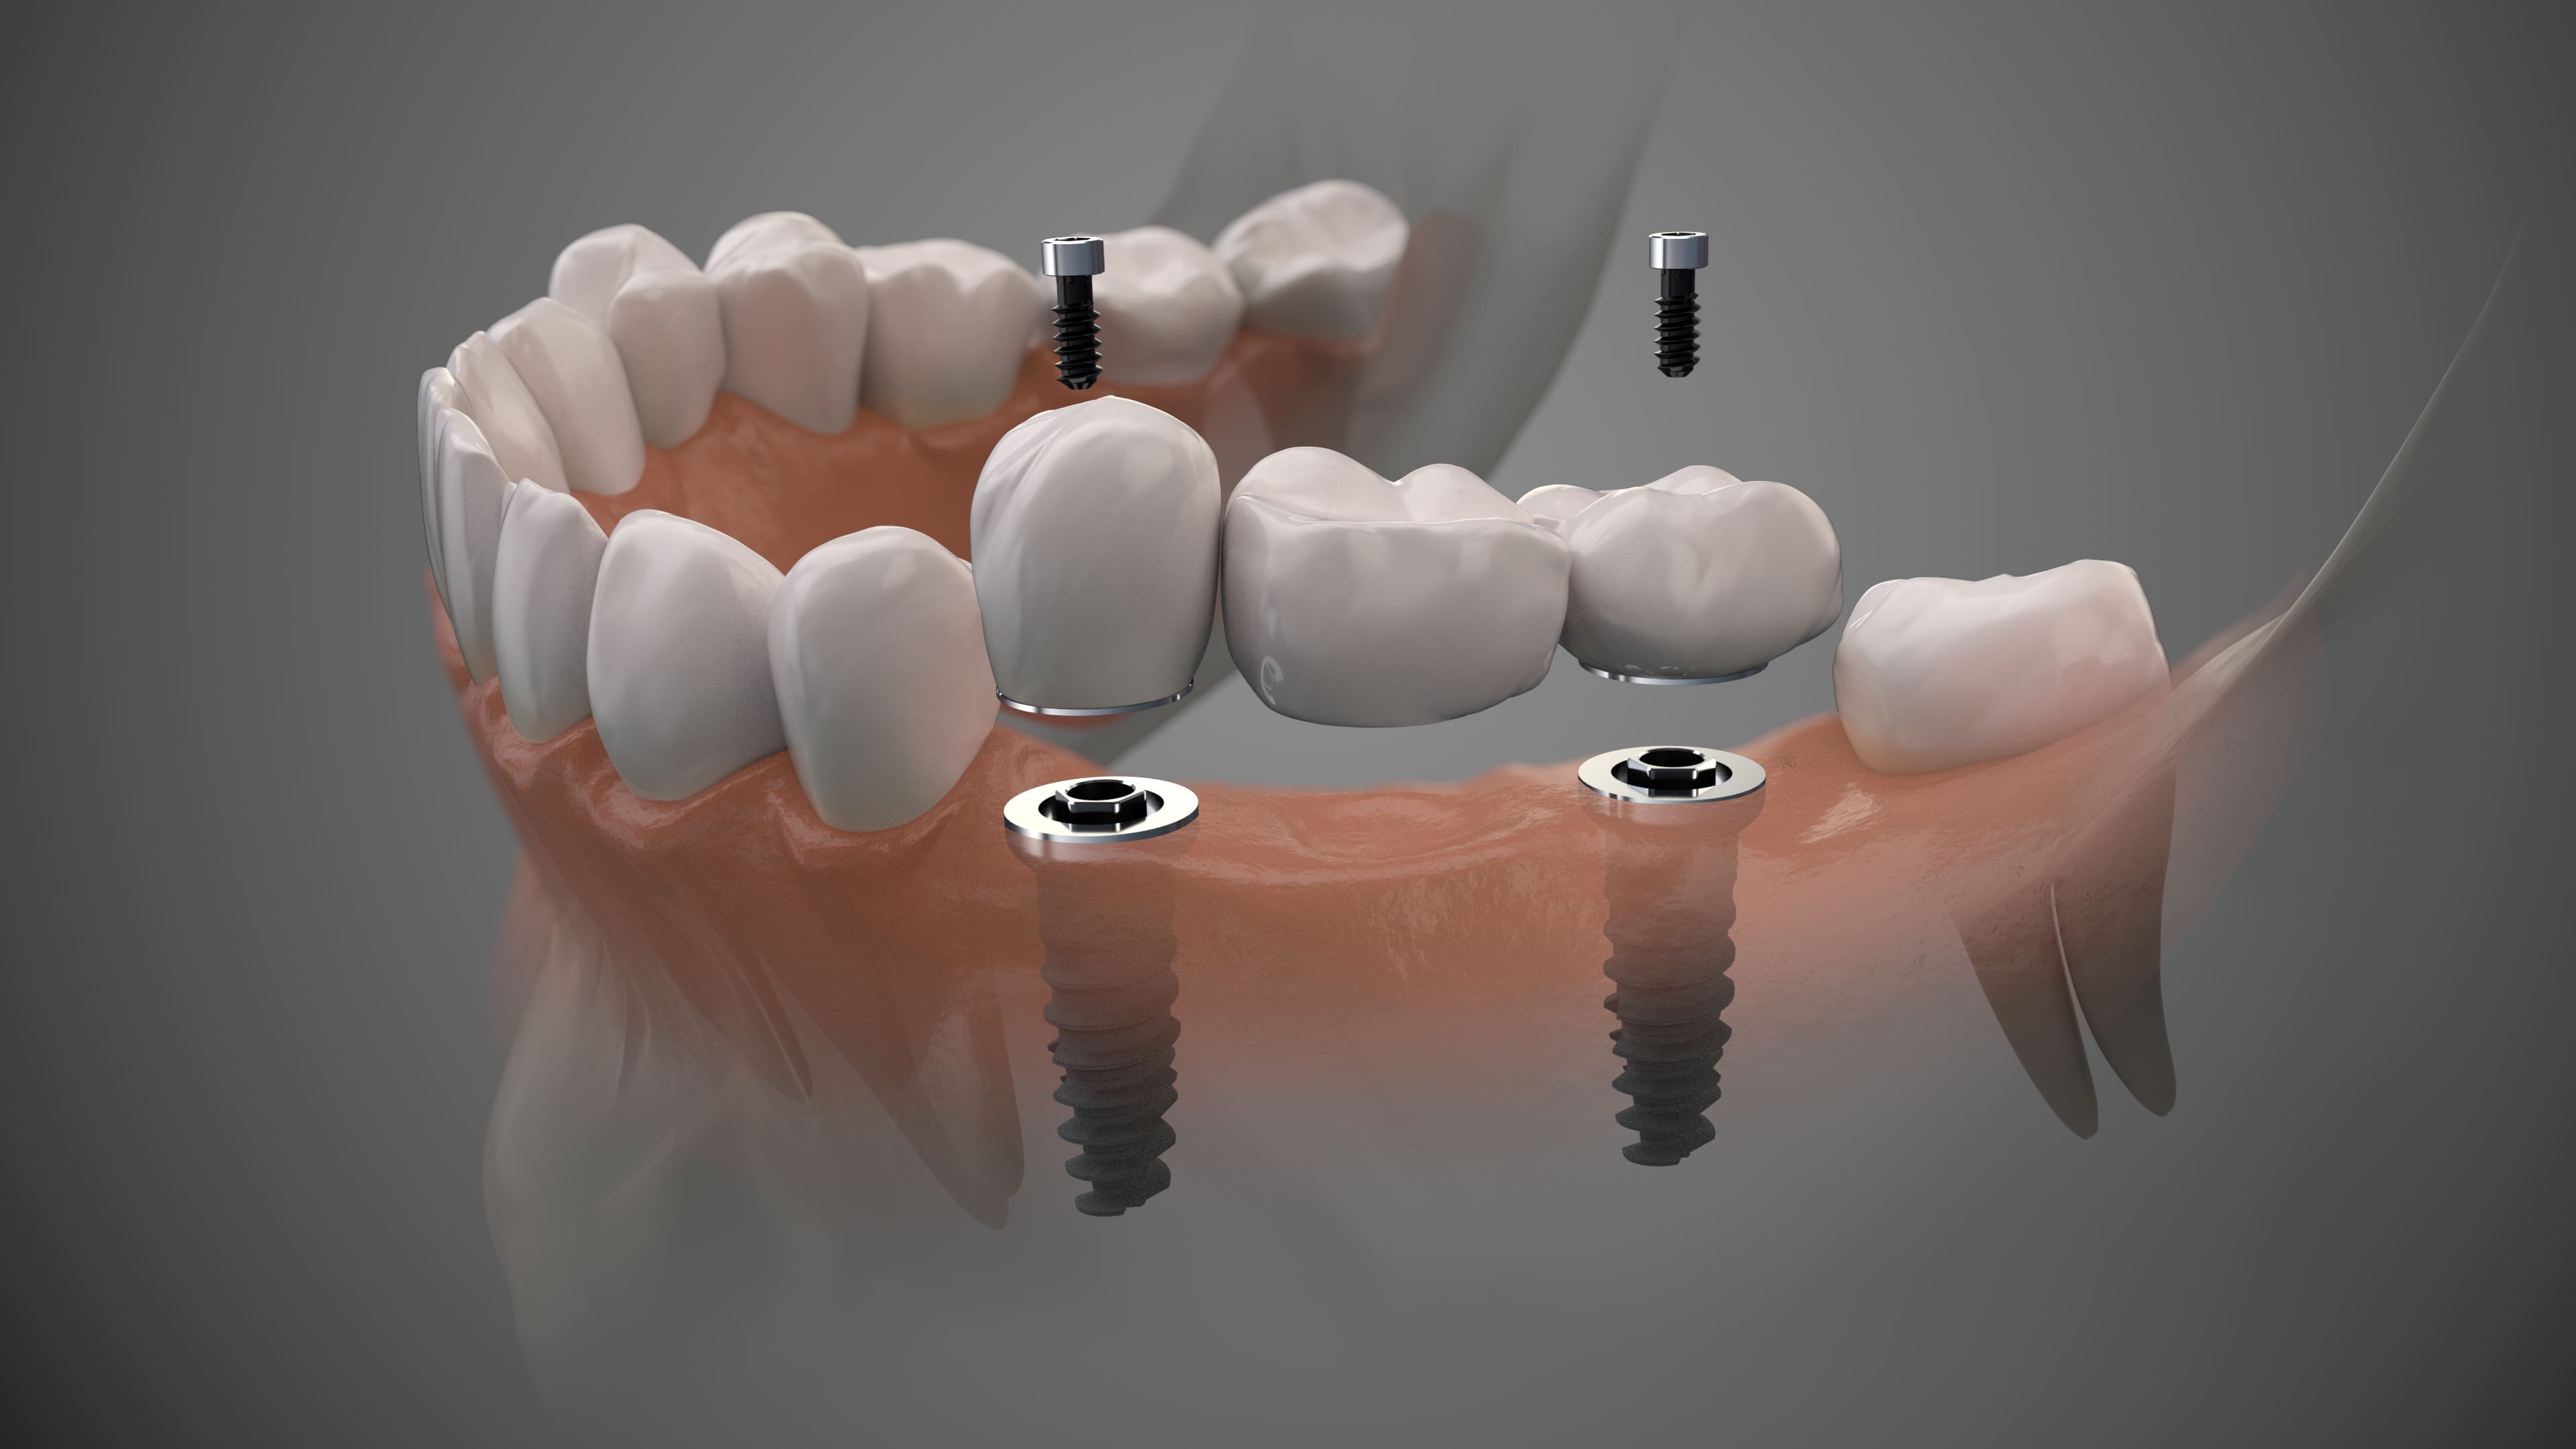

An implant surgical guide is a piece of acrylic resin that fits right over adjacent teeth, with a hole where the implant is to be placed. It is used when a surgeon needs exact guidance as to where in the bone to drill and prepare for the implant procedure. Because the guide is based on digital impressions or imagery, it is very accurate in indicating the correct position and angle for the dental implant. As for most dental treatments, a digital dental implant treatment plan starts with taking a digital image of the oral cavity, often paired with an X-ray image taken with a dental cone beam CT scanner. In addition, some dentists can use simulation software based on 2D images to help the patient understand treatment outcomes. When all data is merged, the digital implant planning can begin.

Identifying the exact position, shape and size of the implants is done with dental 3D software — in this case implant planning software. Once the plan is finalized and approved by the patient, the dental expert can use the implant plan to render surgical guides for implant placement. In the dental implant surgical guide software, the guide appears on the virtual model and when the doctor is satisfied, they can manufacture it either by 3D printing or by milling (a production process where material is shaped using rotary cutters). Now the doctor has a device in their hand, created on digital precision, that fits right over the teeth and that helps the doctor during surgery. It is the starting point of 3D-guided implant surgery.